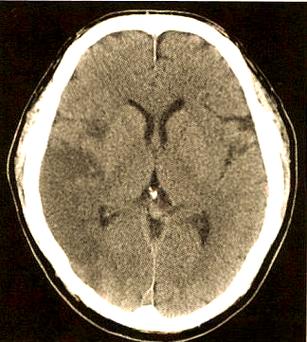

- 影像学特点:头颅CT或MRI上,梗死灶常位于大脑皮层或皮层下分水岭区(即大脑主要动脉供血的交界区),这反映了栓子是从远处随血流冲过来的。